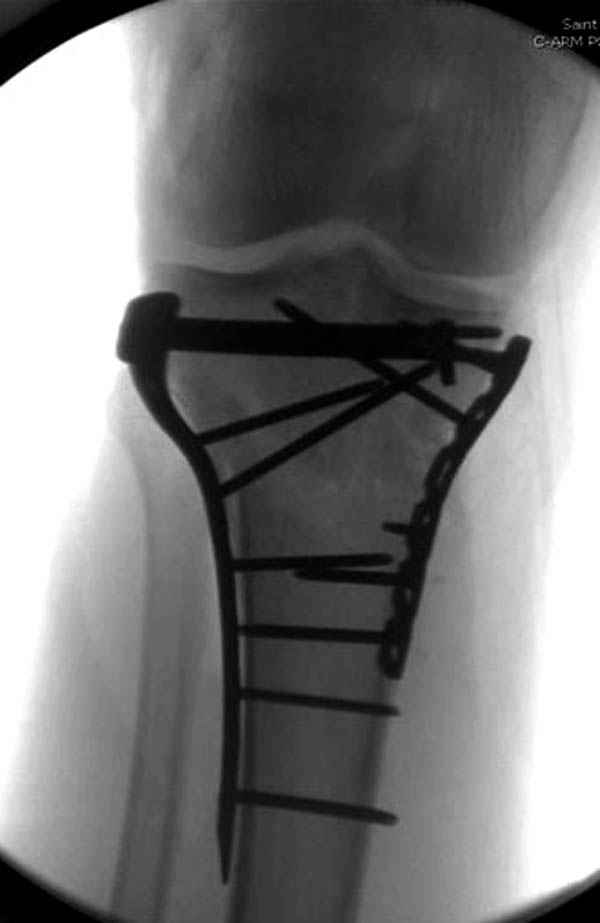

Трудно поверить, что разрекламированная Ортопедическая школа Восточной Украины позволяет такие странные снимки? На прямом снимке сохранен общий контур плато, но не известна судьба импрессии суставной поверхности. На полубоковой?, оставлен без репозиции задне-медиальный отдел, и навряд ли после такой фиксации можно удовлетвориться результатом.

Такая ситуация характерна для многих, когда принимается ошибочное решение, т.е пытаются фиксировать одним имплантом переломы двух мыщелков. Латеральная пластина приемлема только для тех случаев, когда сохраняется интактным медиальный диафизарный кортекс и отсутствует фрагментация на верхушке медиального перелома.

При сложных переломах тибиал плато для своего рода Damage Control мы иногда применяем поэтапную тактику. Сперва оперируется одна сторона, а потом после рекондиции мягких тканей окончательный этап.

Если состояние мягких тканей позволяет, я бы предложил такой метод для вашего больного. Без предварительного планирования будет трудно, но шанс не надо упускать. Всего несколько дней после операции, и такая тактика лучше, чем недовольный молодой пациент.